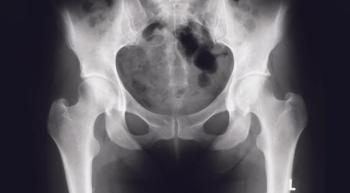

As checkpoint inhibitors have changed the treatment landscape for many cancers, three specific biomarkers identified a subgroup of women with cervical and ovarian cancer tumor types who may benefit from such therapies.

Despite the many advances in cancer care in recent decades, one aspect that hasn’t seen much improvement is the detection of ovarian cancer in its earliest stages. Finding the disease sooner could have a big impact on survival compared with what is experienced with later diagnoses.